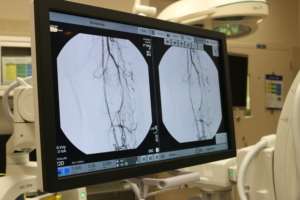

The mobile C-arm uses x-rays to give Dr. Guzman live, high-definition pictures of blood vessels during minimally invasive procedures. “Basically, you need an x-ray picture to see inside the body to thread and manipulate the wires,” he said.

The new three-piece set, manufactured by GE HealthCare, includes the C-arm unit, double touch-screen monitors, and a smaller, portable monitor with controls to move and rotate the C-arm. All the equipment is on caster wheels.